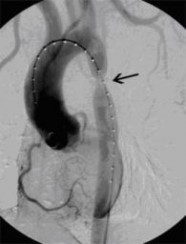

Aortenkoarktationsstenose vor Stentimplantation

(Bild 1 von 4)